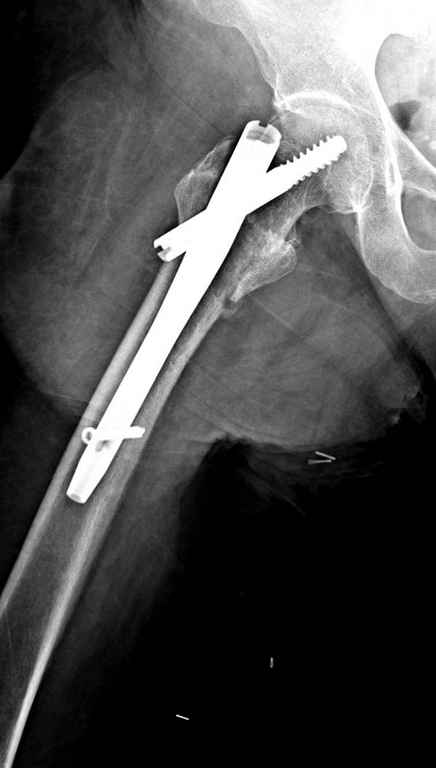

С приходом менее агрессивных блокируемых цефаломедуллярных гвоздей (Gamma 3 и другие) изменилась тактика лечения. Несмотря на то, что вся стабильность держится вокруг одного блокирующего винта, в большинстве случаев гвозди приводили к успеху.

Вашему вниманию представляется похожий случай, пациентке 70, осложнился в течение одного месяца после операции. Ревизия с заменой сустава, кабельная фиксация на трохантер. При установке в дистальном диафизе обнаружен тонкий кортикальный слой и сделана профилактика от возможного перелома аллографтом.